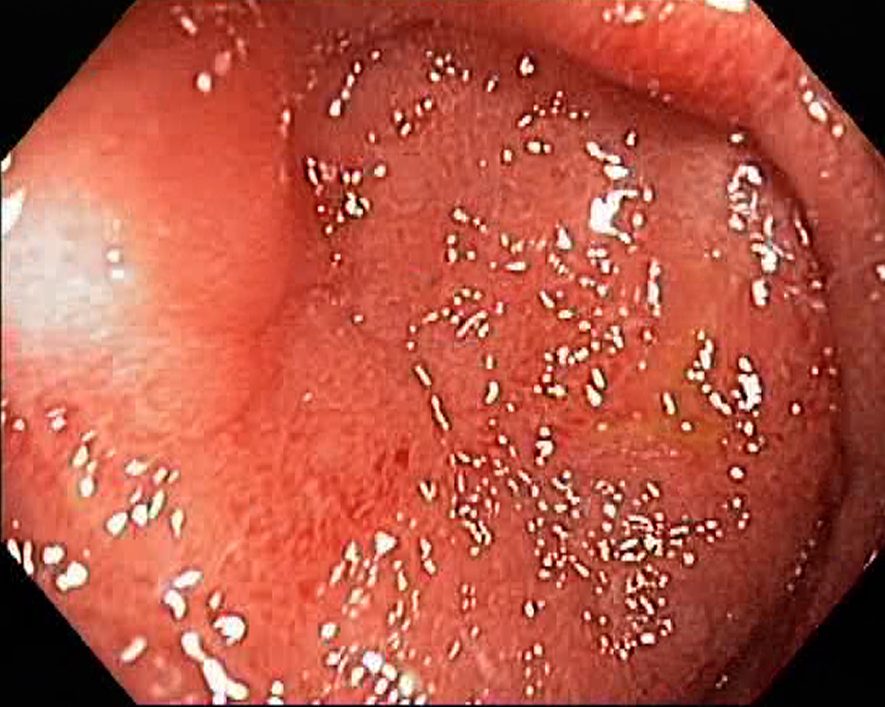

Campylobacter-Colitis

Campylobacter-Colitis. Just click on a picture!